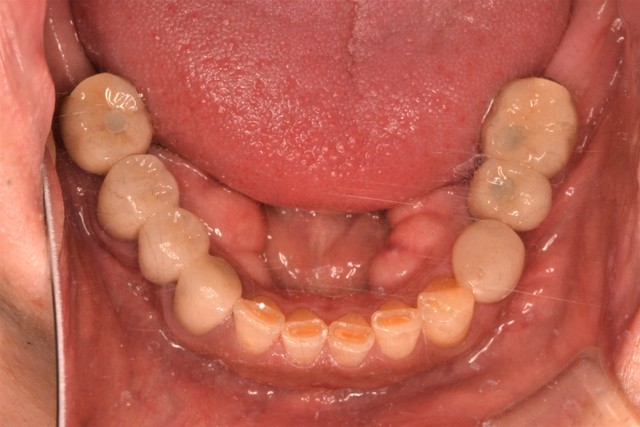

20代 男性

前歯の痛みがあり、虫歯の治療を主訴として来院されました。虫歯が多く、奥歯でしっかりものが噛めない状態でした。歯をなくしてしまっているところを含めて全体的に治療していく計画を立てさせていただきました。

術後1か月

奥歯の大きな虫歯も、丁寧に治療してあげることにより、かみ合わせをしっかり作ることができました。歯がなくて必要なところは1本インプラントを入れ、歯の連続性を健全に整えました。

インプラント以外は、すべて保険の治療です。ひとりひとりに合わせて、一番重要なことを最優先させながら治療計画を話し合っていきます。

奥歯をしっかりと噛めるようになれば、前歯へのかみ合わせの負担も少なくなり、お口の状態の永続性を高めることができます。

インプラントは歯の連続性を保ち、咬合を確立して、噛み合わせ全体のバランスを整えるとても有効な手段のひとつです。周囲の歯を削らずに、インプラント単体で、かみ合わせを支持できることは、長期的な予後にもつながります。